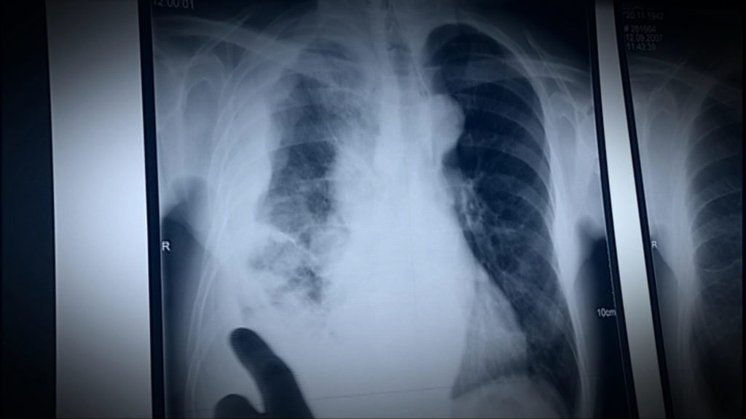

Nordjyske kræftpakkeforløb står nærmest i stampe - især to kræftområder er i søgelyset

NORDJYLLAND: Samlet set går det fremad. Flere nordjyske kræftpatienter behandles til tiden. Det viser nye tal for 2018.